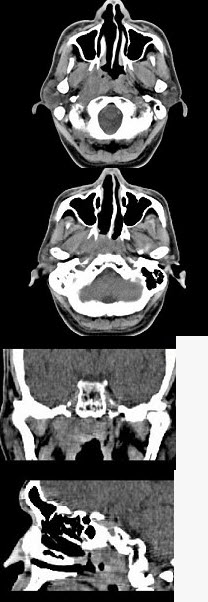

男,52岁,血涕3月余。CT如图所示,最可能的诊断为()。

A、鼻咽癌

B、咽旁混合瘤

C、咽部神经纤维瘤

D、小唾液腺瘤

E、咽旁脓肿

A